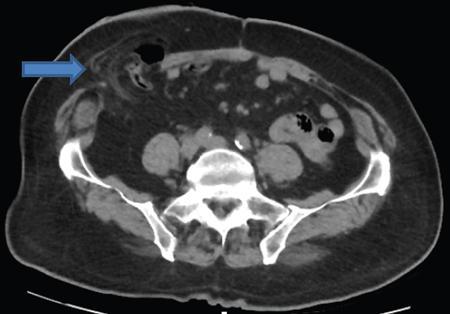

Amandeep Singh The abdominal wall surrounds the anterolateral aspect of the abdominal cavity, where many important organs are located. The abdominal wall is made up of: Superior epigastric artery, inferior epigastric artery, deep circumflex iliac vessels, superficial epigastric vessels and superficial circumflex iliac vessels supply the anterior abdominal wall. Nerves of the anterior abdominal wall include subcostal nerve, iliohypogastric and ilioinguinal nerves. Types of abdominal hernias: The diagnosis of hernia can be made with plain radiographs, barium studies and CT. They consist of a peritoneal sac which protrudes through a weakness/defect in the muscular layers of the abdominal wall (mainly in transversalis fascia below the conjoined tendon). Preperitoneal fat, greater omentum and viscera may protrude into the sac (Fig. 7.15.2). Types: Indirect or direct (depending on their relationship to the inferior epigastric vessels). Indirect hernia: They occur in infants and children. The peritoneal sac passes through the internal ring into inguinal canal, lateral to the inferior epigastric vessels and anterior to the spermatic cord. In women, it goes along the round ligament into the labium. Rarely, the herniated sac instead of leaving the external inguinal ring continues along with the abdominal wall muscles. This is called interparietal hernia (Fig. 7.15.3). Direct hernia: It is always acquired. The herniated sac is medial to the inferior epigastric vessels and does not pass through the inguinal canal. Hence, they do not reach up to scrotum. Femoral hernias are less common than inguinal hernias. They are more common in paediatric age groups and women. The predisposing feature is the empty space between the lacunar ligament medially and the femoral vein laterally. Physical changes of pregnancy dilate this space. The herniated sac is below the inguinal ligament and lateral to the femoral vessels. Strangulation is a common complication. In femoral hernia, the sac lies below and lateral to the pubic tubercle as it emerges from the femoral canal. It can be differentiated from an inguinal hernia which lies above and medial to the pubic tubercle (Fig. 7.15.4). Incisional hernias occur as a result of complication of laparotomy. Risk factors include old age, obesity, postoperative wound infection, chronic pulmonary disease, cirrhosis, malignant tumour, steroids and malnutrition. Most of these hernias develop during the first few months after surgery but may remain silent for up to a period of 5 years. Incisional hernia are more likely to occur as a result of vertical incisions than transverse incisions. They may occur following incisions as small as a puncture site for laparoscopic surgery. A common variation is the parastomal hernia, in which bowel and omental fat protrude through a defect immediately adjacent to an ileostomy or colostomy opening. Bowel loops may be incorporated into the hernia and become incarcerated or strangulated, if the hernia is not treated (Fig. 7.15.5). Richter’s hernia is a rare type of hernia which includes only a part of the bowel wall. Because only a portion of the intestinal wall is included into the hernia, therefore, the lumen remains patent and does not result in obstruction. However, incarceration is not common. Any hernia which contains a Meckel’s diverticulum is known as Littre hernia. They may occur due to the presence of inflammatory adhesions that cause confinement of the Meckel’s diverticulum within the hernia sac. Approximately 50% of Littre hernias develop in the inguinal region, 20% in the femoral, 20% in umbilical and 10% in other sites. Spigelian hernia is a rare acquired ventral hernia that occurs through the linea semilunaris, the line where lateral rectus sheath is formed by fusion of sheaths of lateral abdominal muscles. They are almost always found just above the point where posterior wall of the rectus sheath is pierced by the inferior epigastric vessels. It occurs at midpoint between the umbilicus and symphysis pubis, which is a weak point along the lateral border of the rectus muscle. They are rare but have a high frequency of incarceration and strangulation. It may be mistaken for an abdominal wall lipoma, if it contains only peritoneal fat. CT can be quite beneficial to confirm the diagnosis (Fig. 7.15.6).